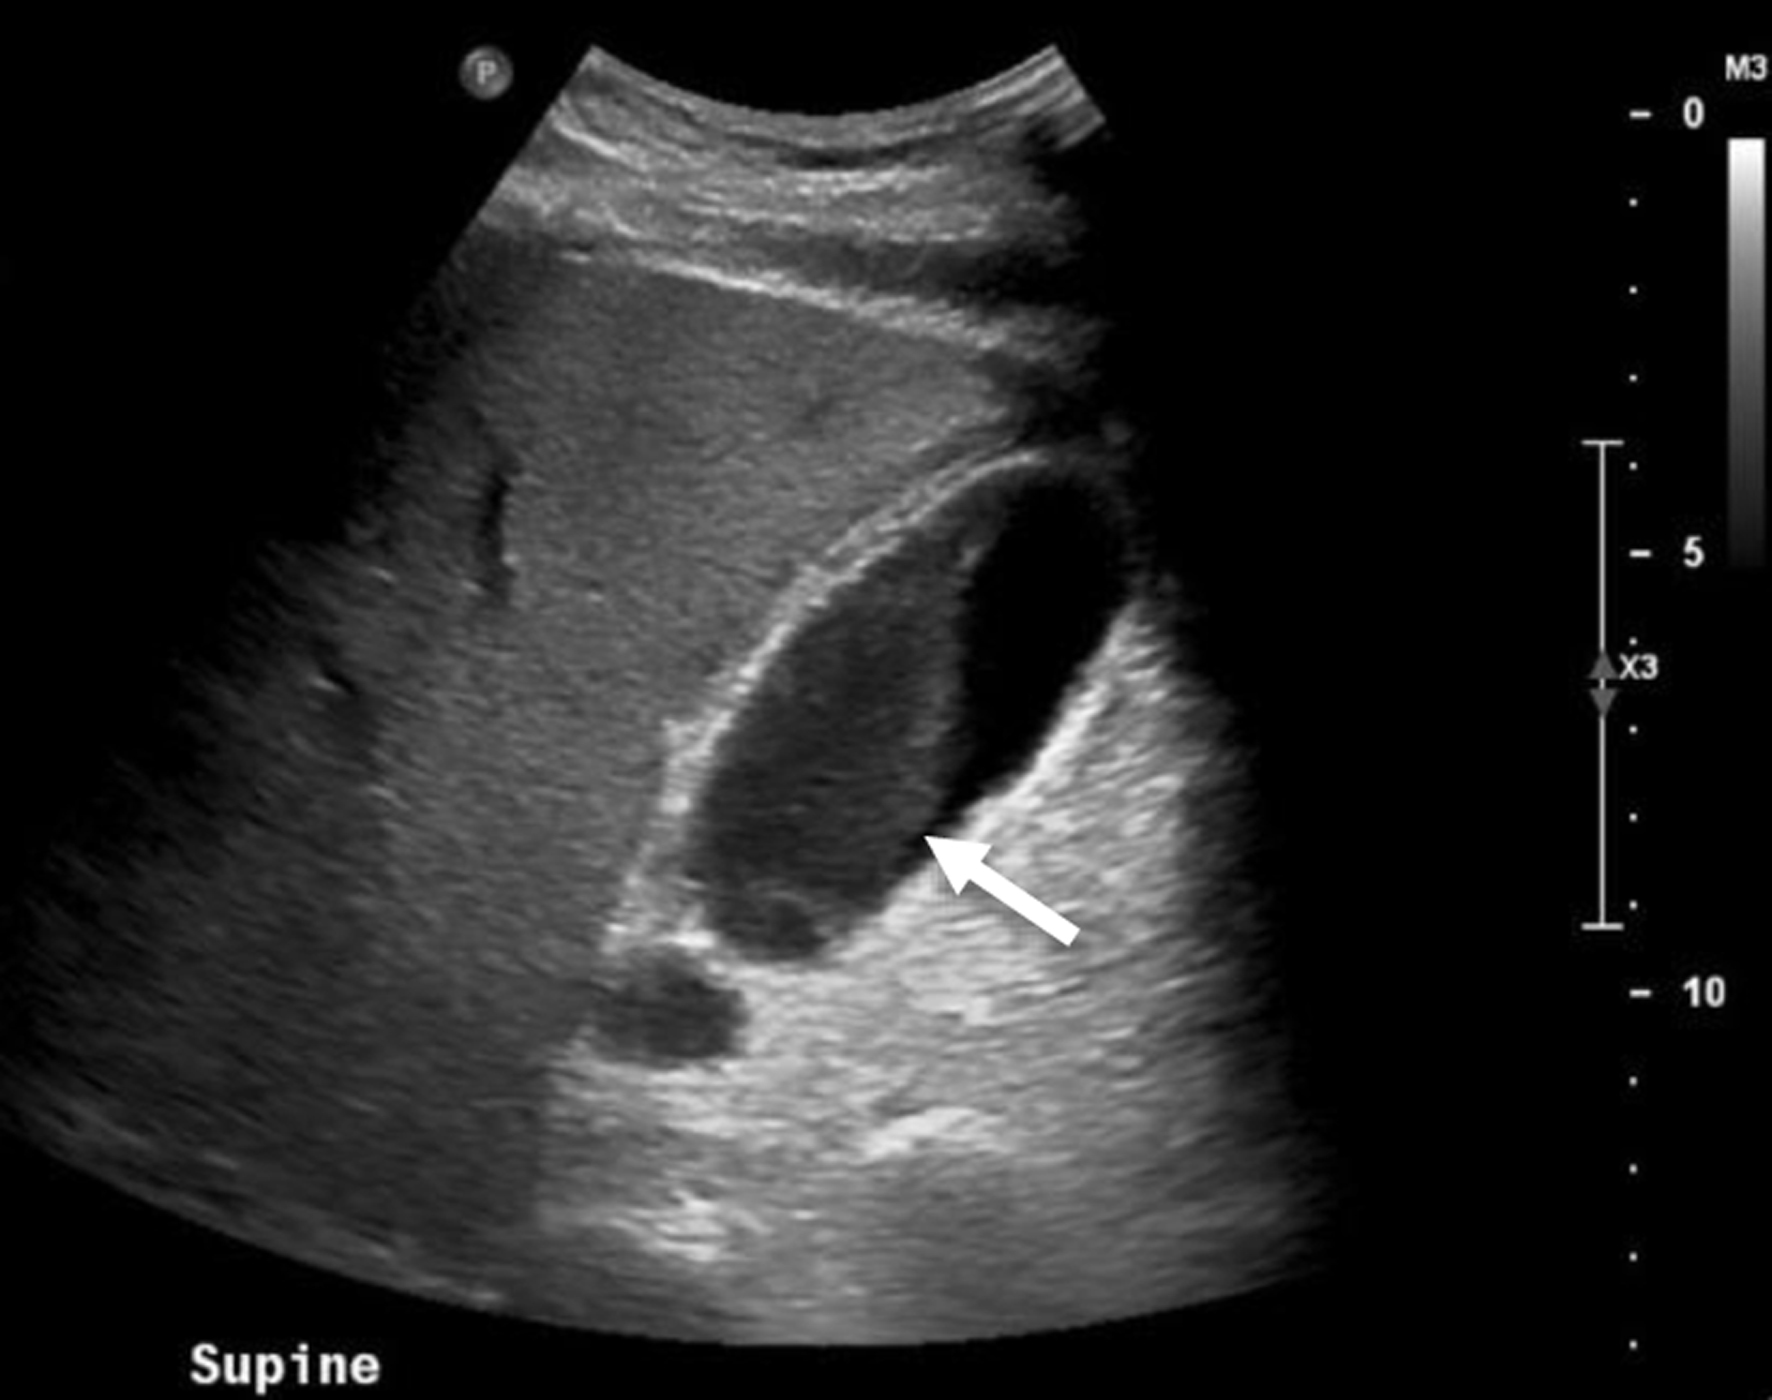

On exam, his abdominal right upper quadrant was non-tender, epigastric area was moderately tender to palpation, and he had a negative Murphy’s sign. Ultrasound showed evidence of gallbladder wall thickening (4.3 mm, normal < 3 mm), non-dilated common bile duct (3.9 mm, normal < 6 mm), gallbladder sludge, and no appreciable gallstones (Fig. 1). Computed tomography (CT) of abdomen and pelvis without contrast showed moderate gallbladder wall thickening with inflammatory changes in the surrounding fat and cholelithiasis (Fig. 2). At this time, labs showed no leukocytosis, non-elevated LFTs, and non-elevated lipase (Table 1). Otherwise, labs were significant for hyperglycemia (glucose 307, reference range 70 - 100 mg/dL) and a calculated anion gap of 19 (reference range 4 - 12 mmol/L) (Table 1). The patient was then admitted for management of DKA.

Click for large image

Figure 1. Abdominal ultrasound of the patient displaying thickened gallbladder wall (diameter 4.3 mm, normal < 3 mm) as well as sludge within the gallbladder. Arrow points to sludge within gallbladder.